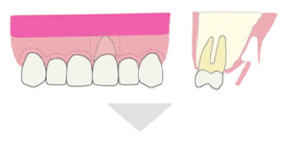

特徴5:治療後、美しい口元に改善する「歯肉移植術」

歯周病が進行すると、顎の骨が徐々に吸収されるとともに、炎症によって歯肉が腫れ上がります。骨の吸収が進めば歯肉は下がり、歯根が露出して歯が長く見える状態になりますが、炎症による腫れによって外見上はその変化が分かりにくくなります。治療によって炎症が改善されると、腫れが引き、隠れていた歯の部分が見えるようになるため、結果として「歯が長くなった」ように見えるのです。

当院では、治療後に審美的な見た目が気になる場合の改善策として「歯肉移植術」を実施しています。これは上顎の健康な歯肉の一部を採取し、見た目の改善が必要な部位に移植する方法で、歯肉ラインの回復と審美性の向上を目的としています。

Step1 歯肉の採取:上顎の奥歯の内側から移植する歯肉を採取します。

Step2 歯肉の移植:移植する箇所の歯茎を切開し、その中に採取した歯肉を入れます。

Step3 歯茎の縫合

歯肉を採取するために切開した歯茎は2週間程度でもとどおりになり、移植された歯茎はおよそ1ヶ月程度で傷跡がなくなり、周囲の歯茎と区別がつかない自然な状態になります。